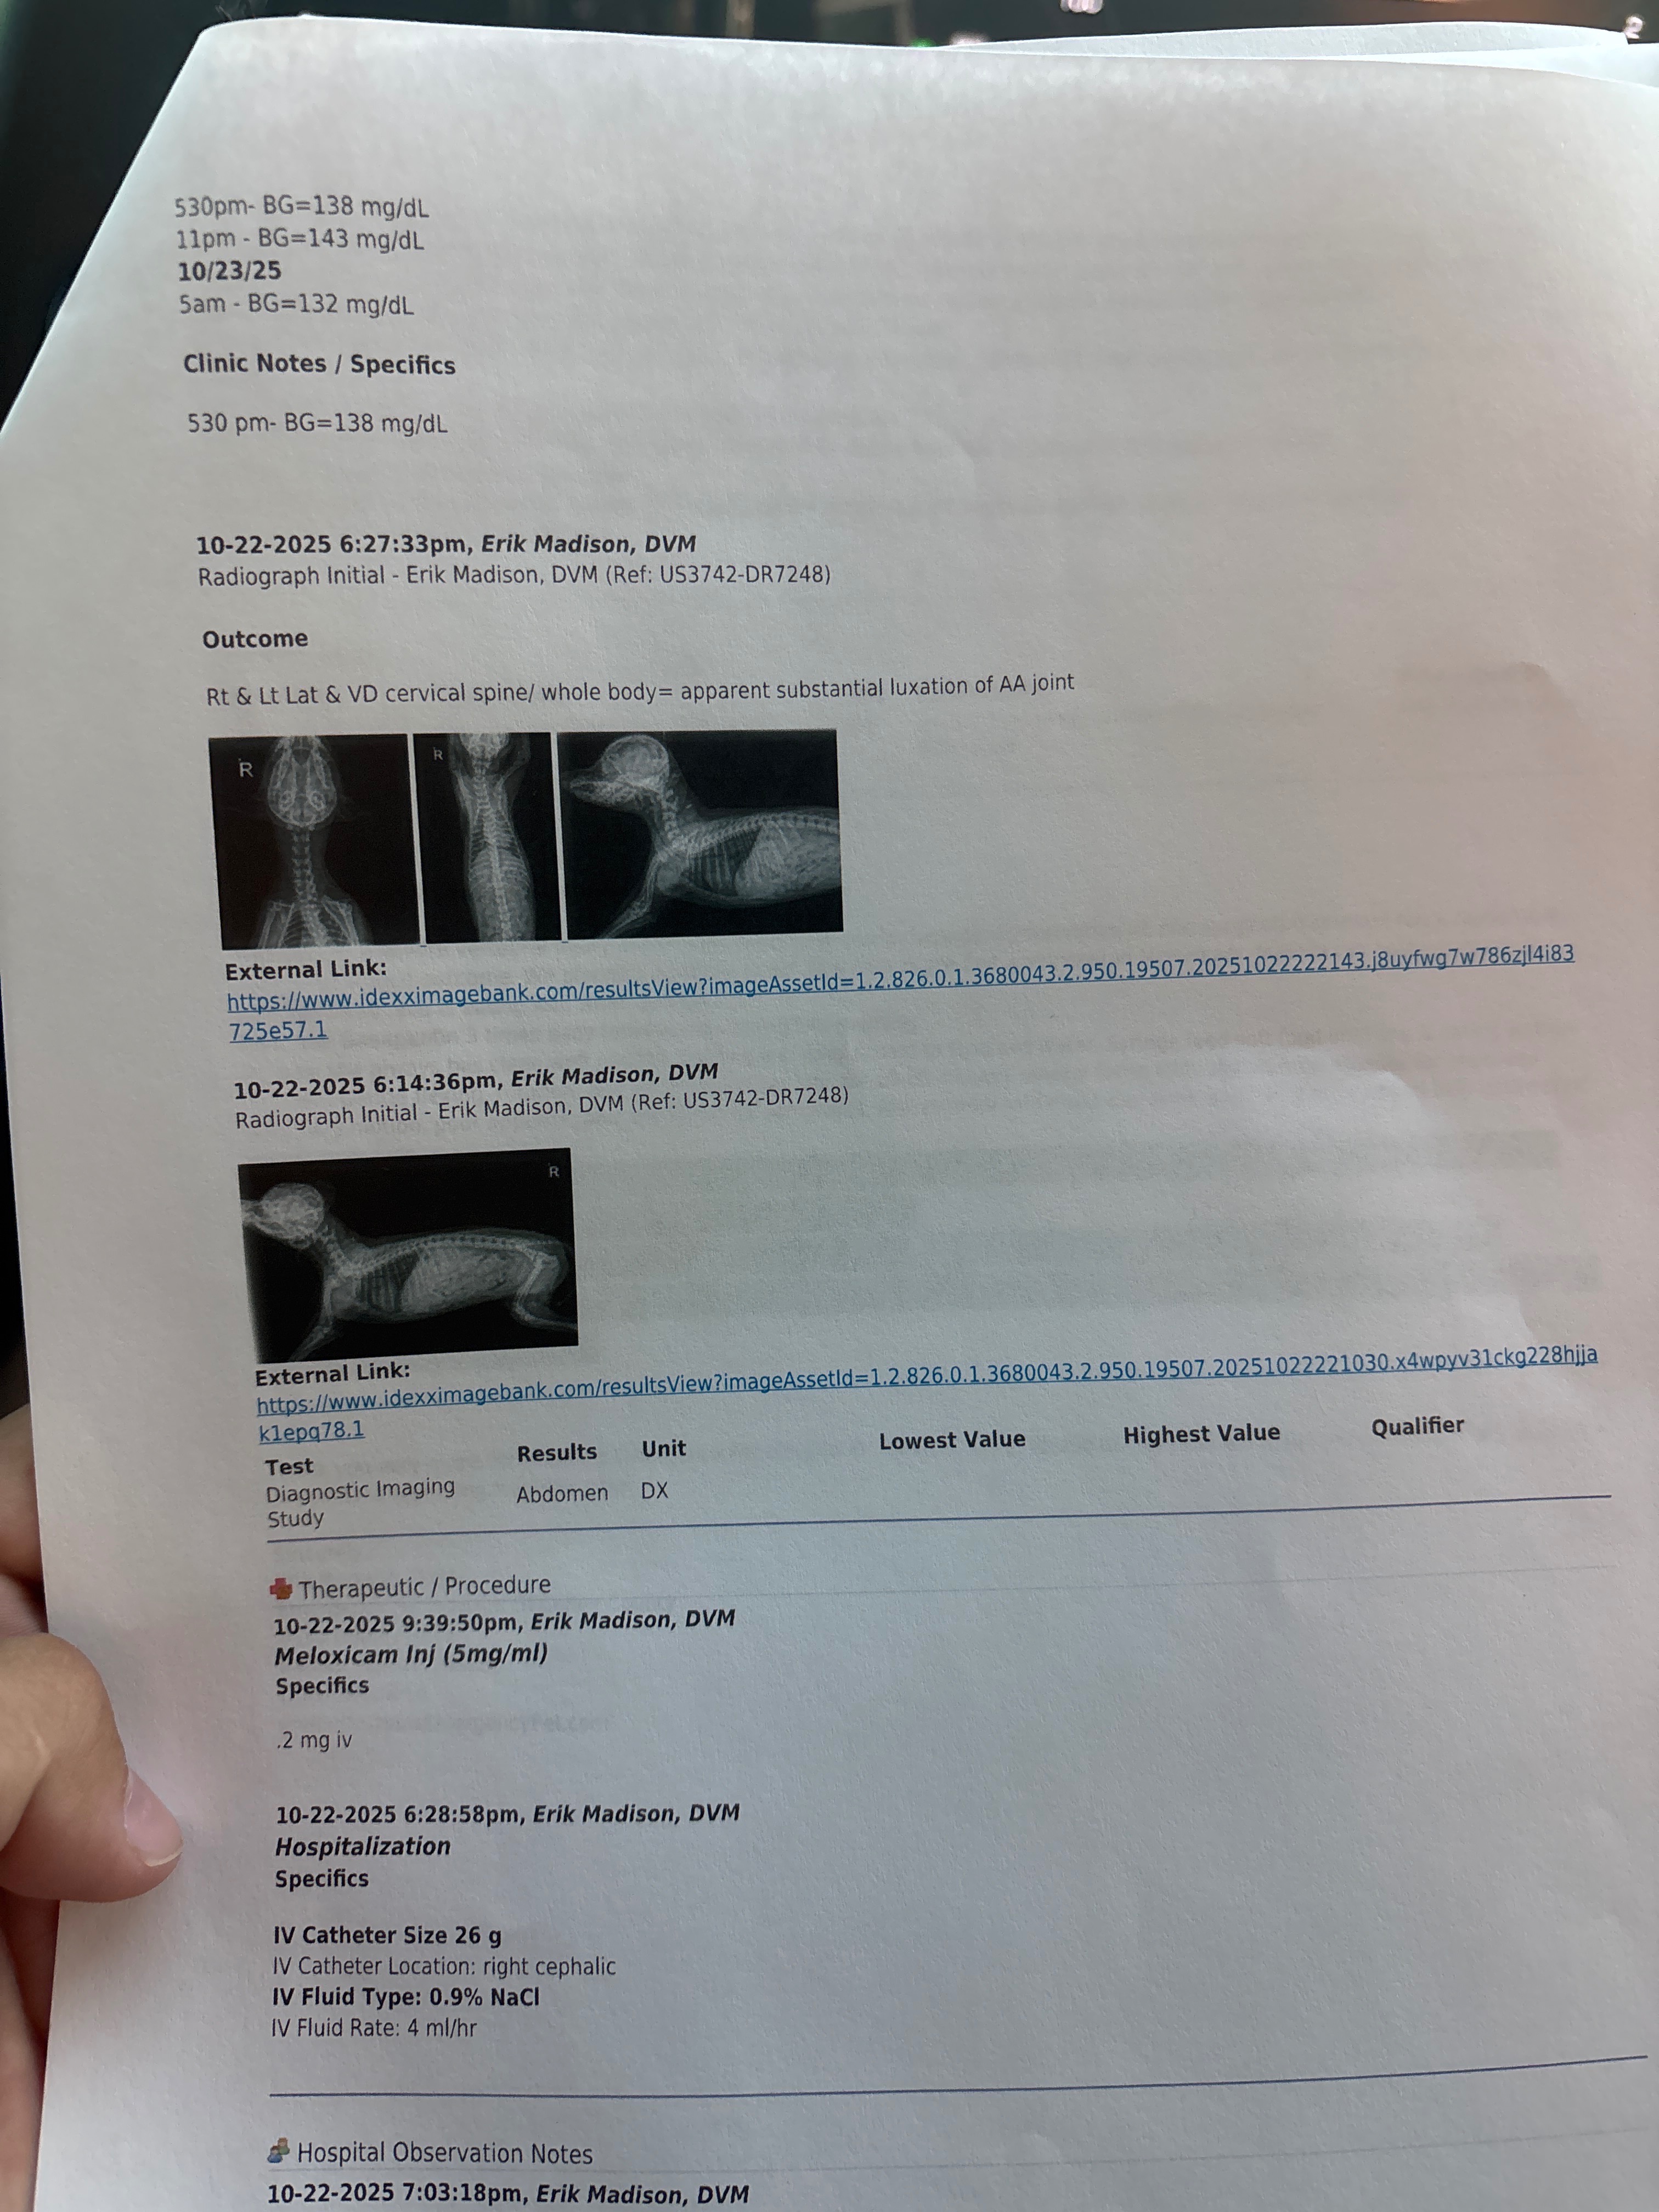

My heart is breaking. Sweet 8-week-old toy poodle, Matilda, broke her neck in two places. She’s just a baby… So full of love and life & now she can’t move her little legs. But since she is so young the specialist thinks there is still a chance.

The vets say there’s hope if she can get the right care and time to heal. I just want to give her that chance’s to grow up, to play, and to live the happy life she deserves.